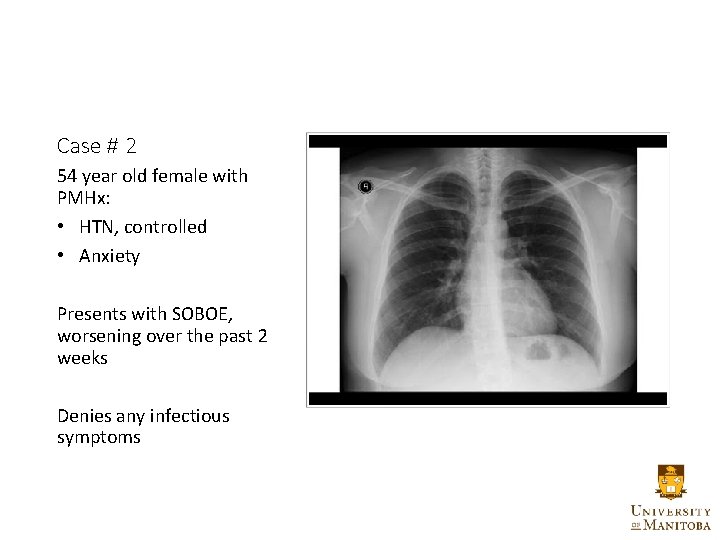

Case # 2 54 year old female with PMHx: • HTN, controlled • Anxiety Presents with SOBOE, worsening over the past 2 weeks Denies any infectious symptoms